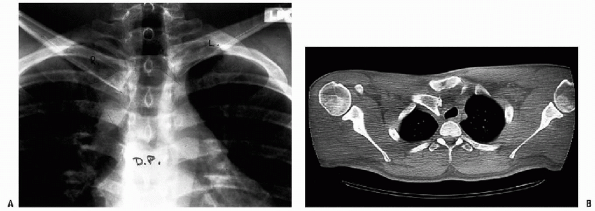

CT is the best radiographic study for evaluating SC joint injuries (Fig. 20-6).-

It can show fractures of the medial clavicle, physeal injuries, and subtle subluxations.

| Figure 20-6 A: Routine AP x-ray of posteriorly dislocated right SC joint. B: The AP view is suggestive of a posterior dislocation. However, the CT scan clearly demonstrates the posteriorly displaced right medial clavicle. Note the displacement of the trachea. (From Bucholz RW, Heckman JD. Rockwood and Green’s Fractures in Adults, 5th ed. Lippincott Williams & Wilkins, 2001.) |